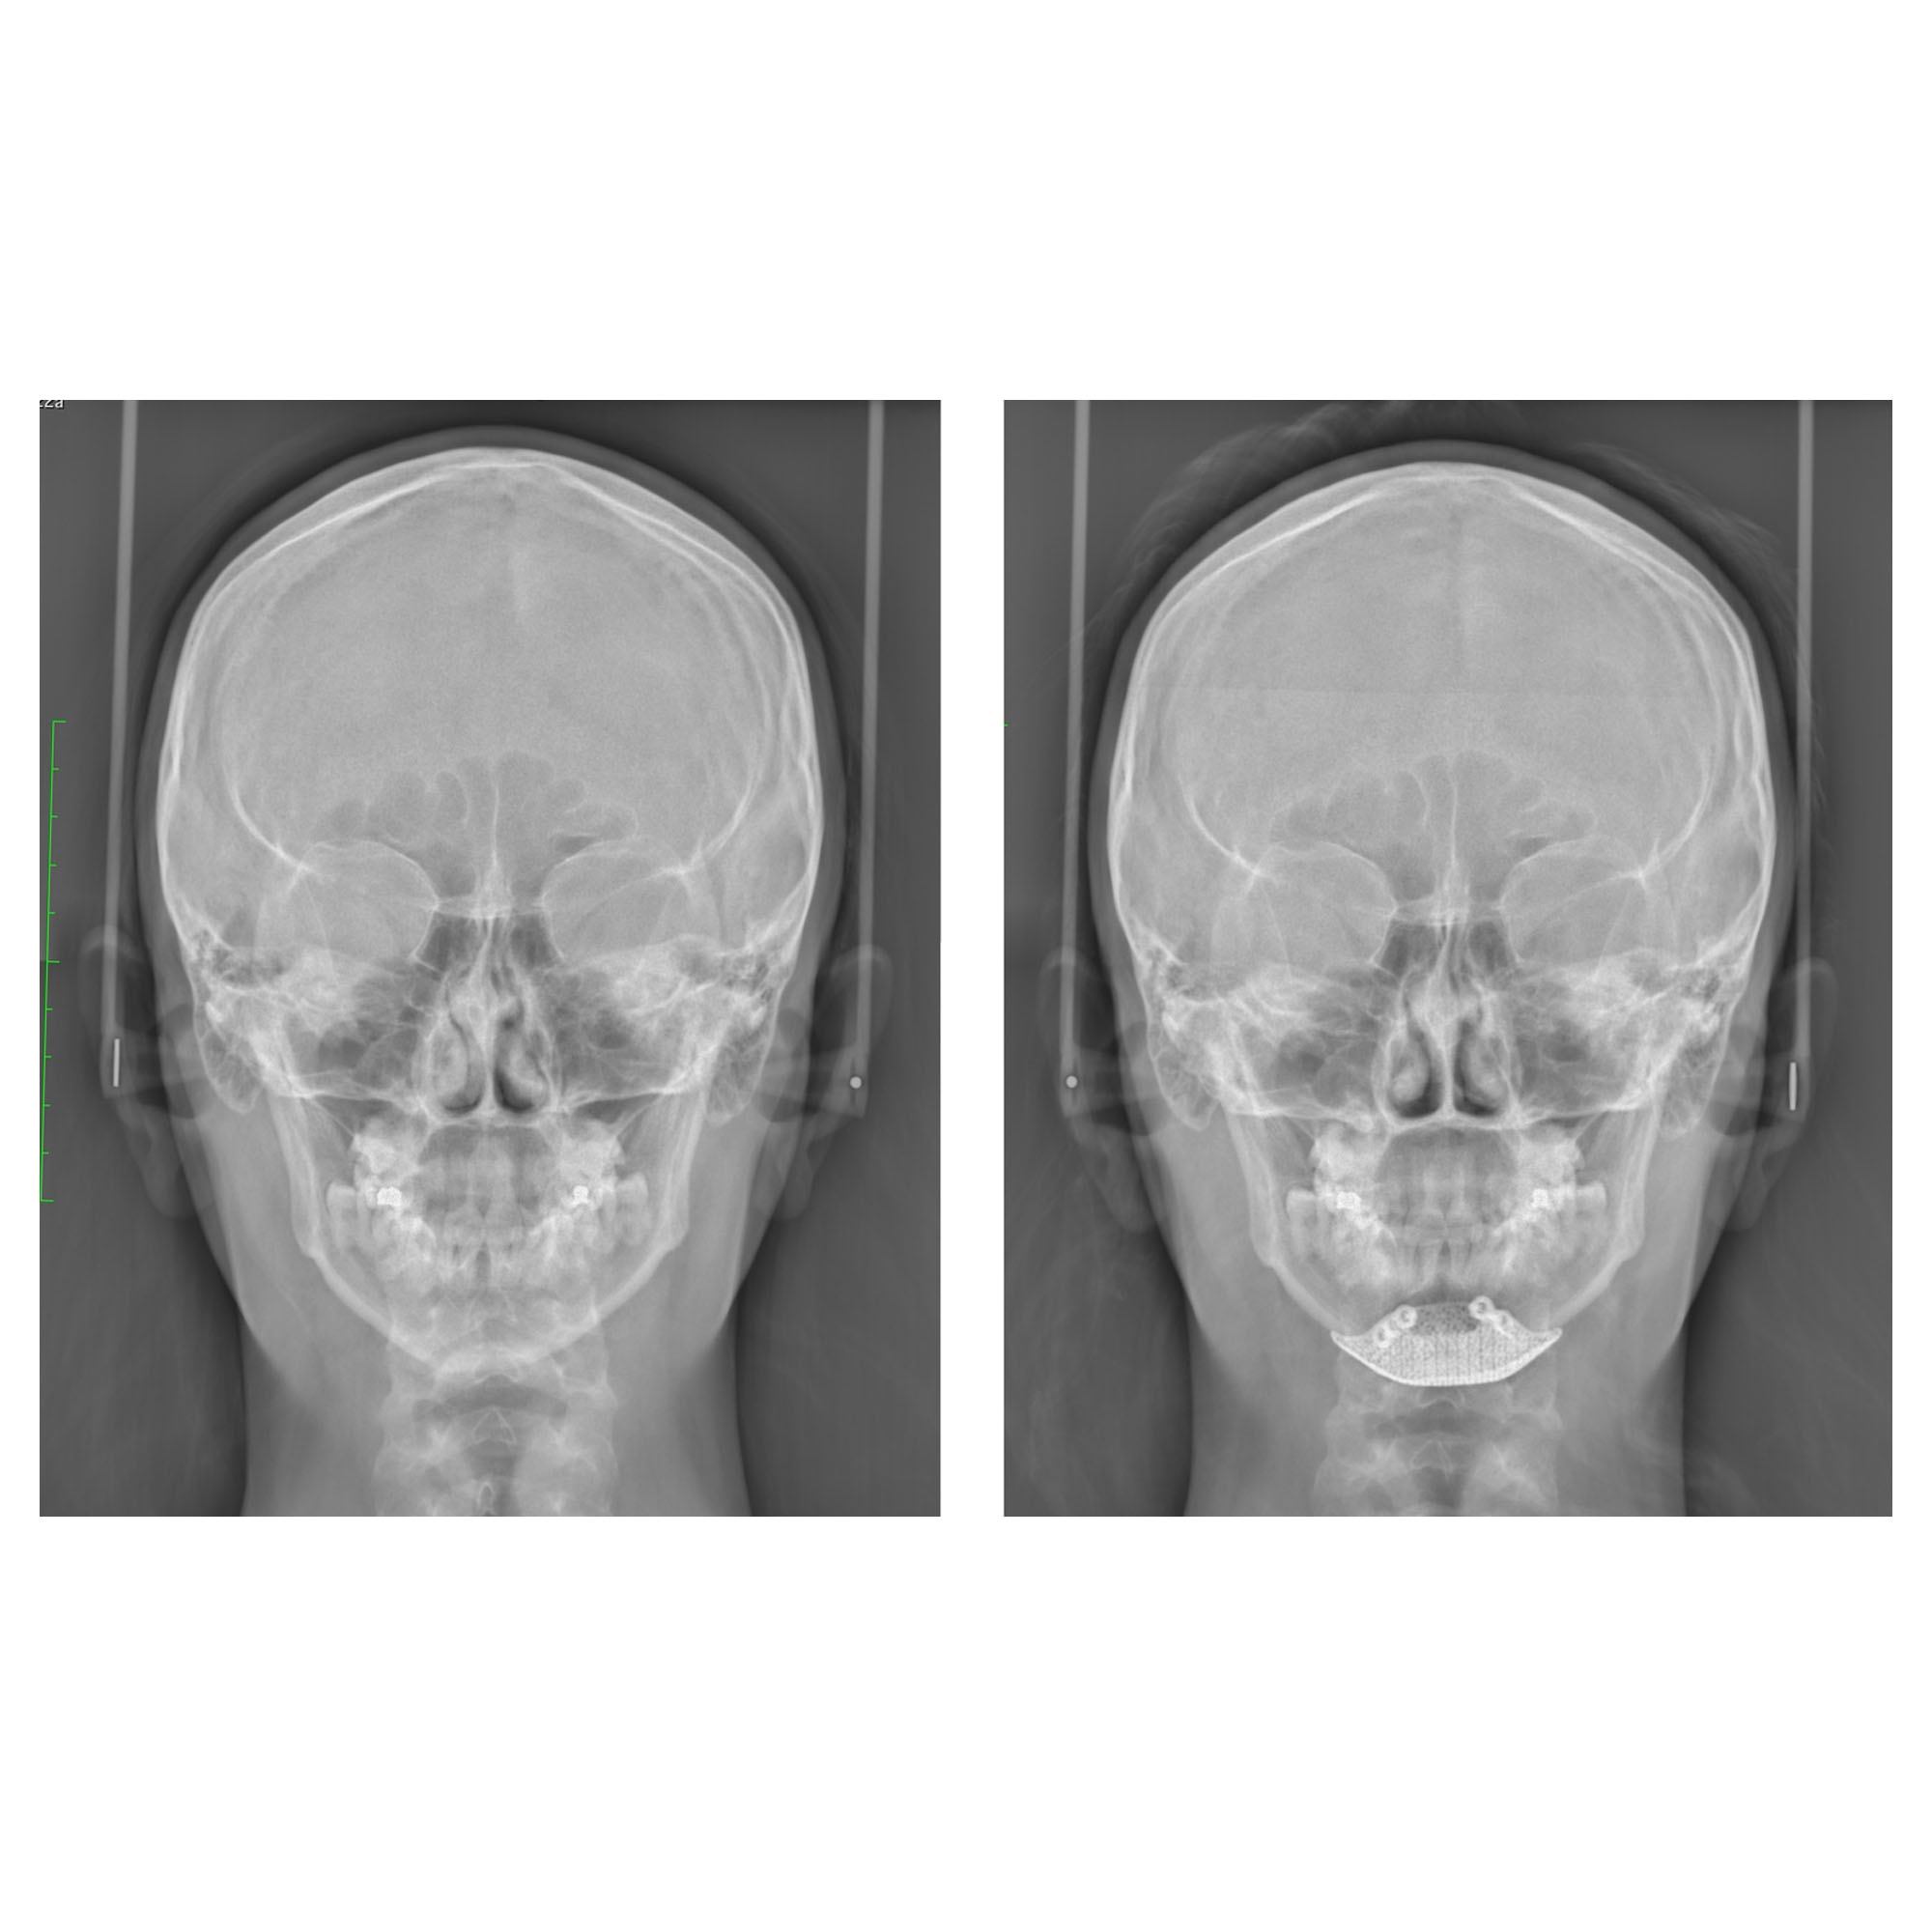

Comme on l’observe sur les radiographies ci-dessous, la chirurgie du menton osseuse permet de fixer avec une grande précision l’os du menton et d’utiliser cette opération pour obtenir un résultat d’une parfaite stabilité dans le temps, avec un potentiel esthétique très important. Pour plus d’informations sur les techniques de chirurgie du menton, vous pouvez consulter notre page sur la génioplastie paris.

radios génioplastie Paris

Voici un patient qui avait un menton trop long. La génioplastie a permis de réduire la hauteur tout en conservant une légère avancée esthétique.